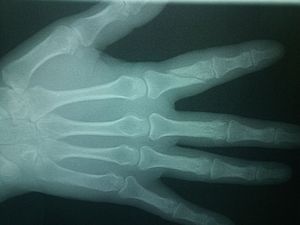

Fracture in the proximal phalanx of the 2nd digit

complete fracture in the proximal area of the second digit

Oblique Fracture in 2nd digit phalanx...? spiral fracture maybe?

Fracture at proximal phalanx , of 2 digit